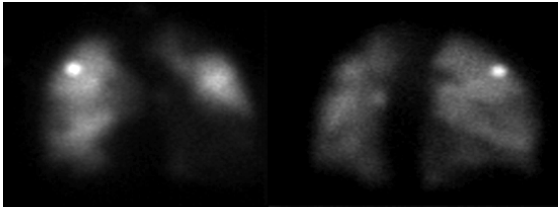

During hospitalization in the general ward, hydrocortisone was discontinued, and bridging anticoagulation therapy was started with warfarin; the patient persisted with lower limb edema and dyspnea episodes, even with diuretic dose adjustment. Given the slow and torpid evolution, the suspicion of pulmonary thromboembolism persisted, so pulmonary perfusion and ventilation (V/Q) scans were requested, which showed multiple segmental perfusion defects that involved the posterior basal and anterior basal faces in the right lower lobe and the lateral surface in the middle lobe. There was also an involvement of the apical segment of the left upper lobe and segments of the lingula. The findings were highly suggestive of bilateral multiple pulmonary thromboembolism (Figures 4 and 5).

Orange arrows: perfusion deficits in the basal anterior, lateral and posterior segments of the right lower lobe, in the apical segment of the left upper lobe, and in segments of the lingula. Source: Document obtained during the course of the study.

Figure 4 Perfusion scintigraphy.

Note: The study could not be performed due to the patient's inability to properly inhale the radiopharmaceutical agent. Source: Document obtained during the course of the study.

Figure 5 Ventilation lung scan.